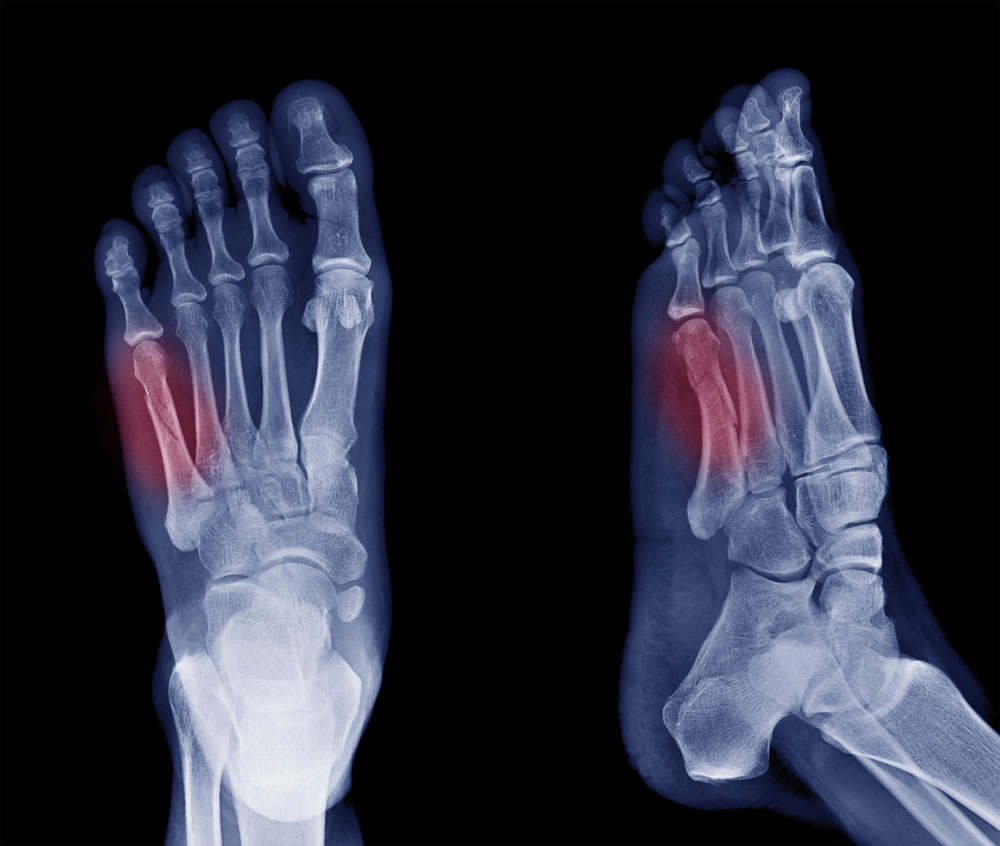

Foot Fracture

A foot fracture refers to a break or crack in one or more of the bones of the foot. Fractures can occur in various parts of the foot, including the toes, metatarsals (long bones in the middle of the foot), and the tarsals (bones in the hindfoot).